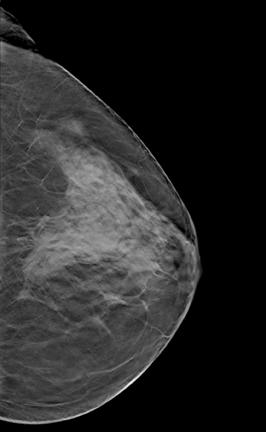

Despite decades of progress in breast imaging, one challenge continues to test even the most skilled radiologists ...

Gamma Medica announced the updated LumaGEM Molecular Breast Imaging (MBI) system.